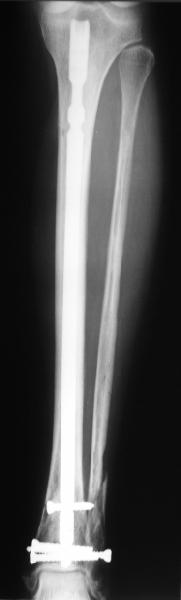

I am just trying to illustrate that prevention of 1)tibial valgus and 2)loss of reduction can be provided without fibular plating. Small changes of conventional nailing techniques allow to maintain reduction of the tibia reliably without adjunctive fibular stabilization.

In delayed cases acute length restoration performed only in the tibia may leave the fibula shortened thus change the mortise. So it is reasonable to restore length of both bones simultaneously by distractor and fix the fibula not with open reduction and plating but just by a single perQ screw. Example attached.

[ Ответить ]